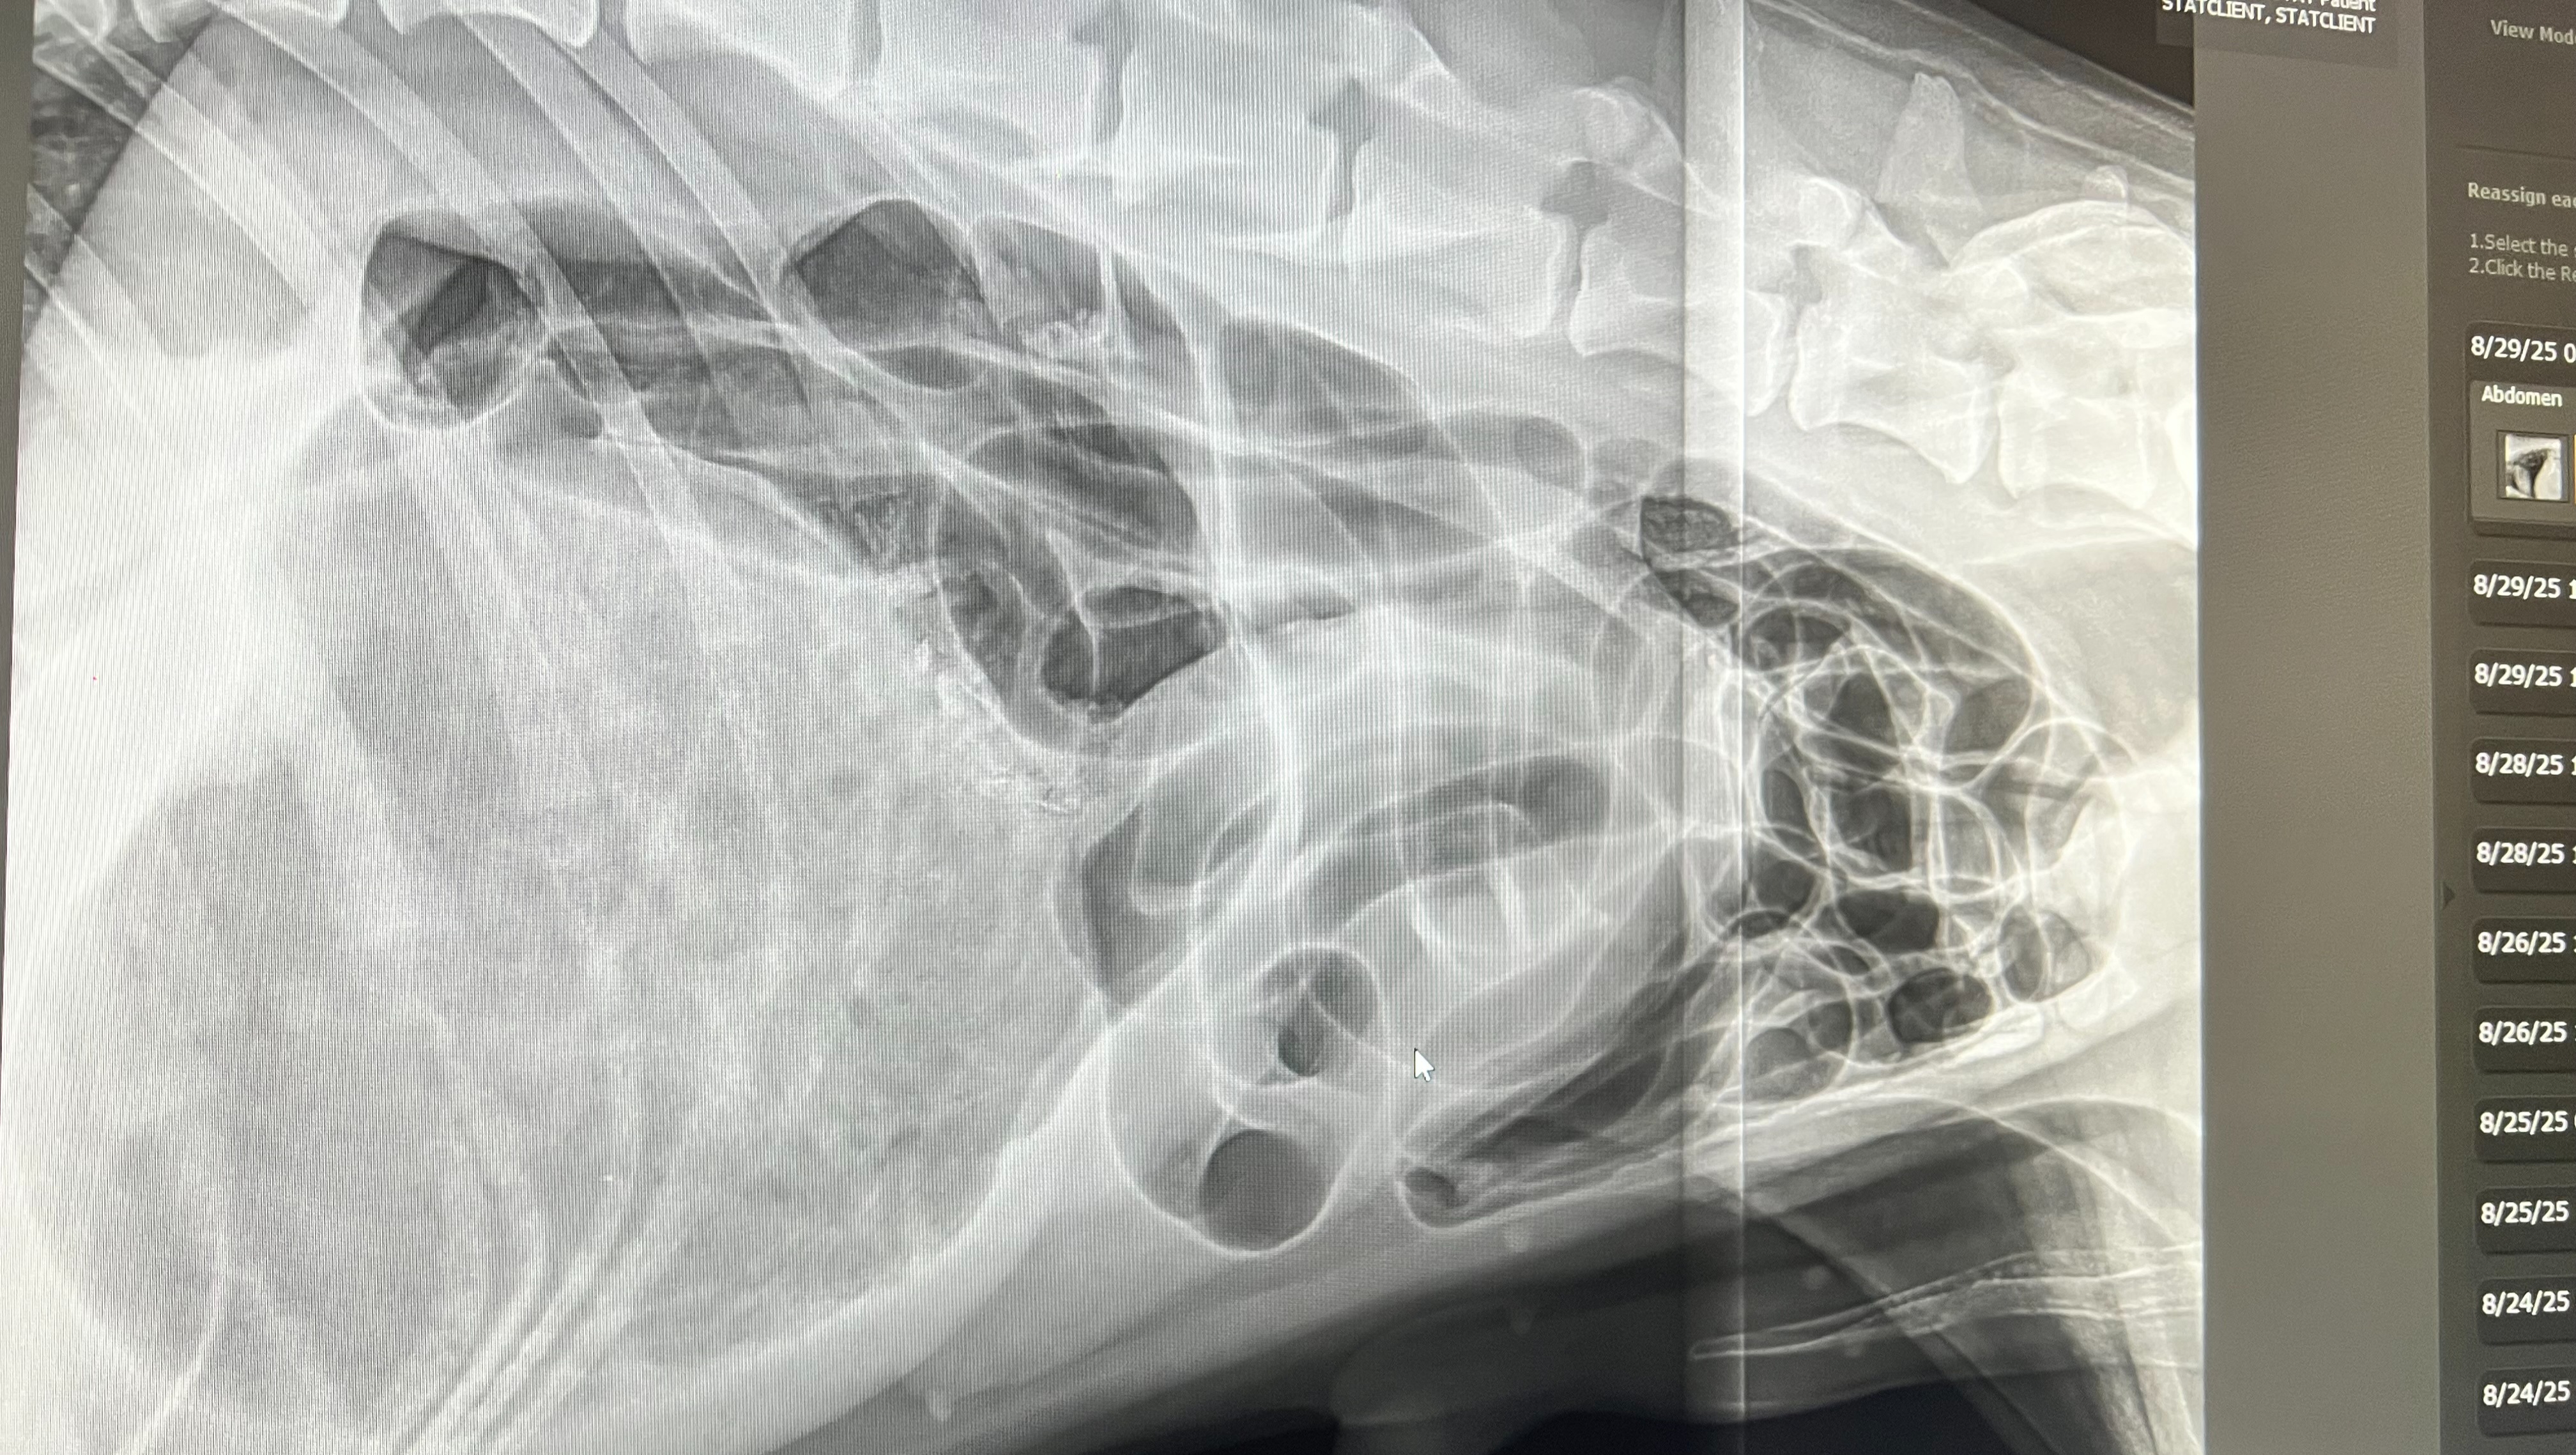

Hello everyone, our dog Apollo recently had surgery from a life-threatening emergency of Bloat or GDV (Gastric Dilatation-Volvulus). GDV is when a dog's stomach fills with gas and then twists on itself, leading to heavy breathing, the inability to vomit, and pain.

As a family, we decided to go through with the surgery despite the financial cost because Apollo is a core member of our family and we would love to extend his life as much as possible. However, this surgery is very expensive. First, we took him to Ocean Avenue Veterinary Hospital in San Francisco to have him checked out which costs $453.60. We then transferred him to SAGE Veterinary Centers in Redwood City where they stabilized and conducted the surgery on him. The stabilization process cost $3913.42 and the surgery cost $10,000. Altogether, the entire process cost $14,367. We are a low-mid income level family and we are unable to afford to pay off this debt in time. In short, we would appreciate any and all contributions to help pay off this debt on our family. Thank you so much and God bless you.